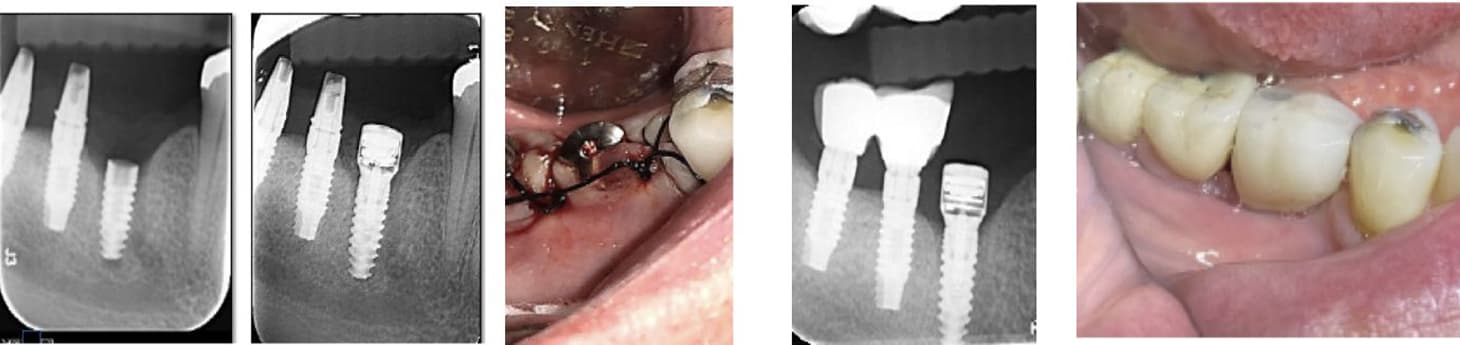

A 71-year-old healthy patient with poor bone quality presented following failure of a previous implant. A new implant was placed using a MED healing abutment to enhance the healing environment and promote bone regeneration. Radiographic evaluation at insertion revealed low bone density around the implant site.

After 60 days, radiographs demonstrated a marked increase in bone density surrounding the implant, indicating successful osseointegration and restoration of bone volume. The improved peri-implant bone quality enabled a stable impression and subsequent prosthetic rehabilitation, confirming the effectiveness of the MED healing abutment in supporting bone regeneration and implant stability in compromised sites.

A 71-year-old healthy patient presented with a fractured implant, which required replacement. A new implant was placed and activated using a MED healing abutment to promote accelerated osseointegration and enhanced bone regeneration. The healing process progressed smoothly, with excellent tissue response and no complications observed.

After 60 days, radiographic and clinical evaluations confirmed complete osseointegration of the newly placed implant. The patient received a definitive crown, demonstrating strong implant stability, healthy peri-implant tissue, and optimal esthetic and functional results, validating the regenerative and acceleration benefits of the MED technology.